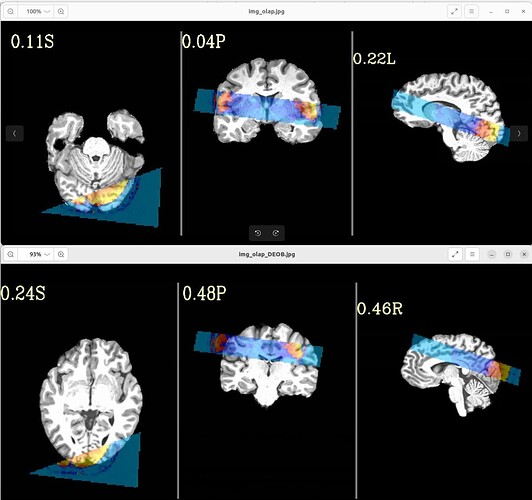

with following images:

Where the DEOB doesn't seem to be correct.